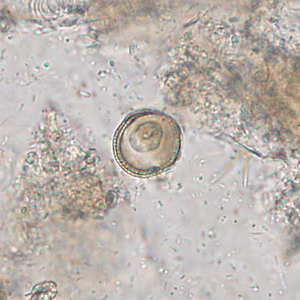

DPDx is an educational resource designed for health professionals and laboratory scientists. For an overview including prevention, control, and treatment visit www.cdc.gov/parasites/.